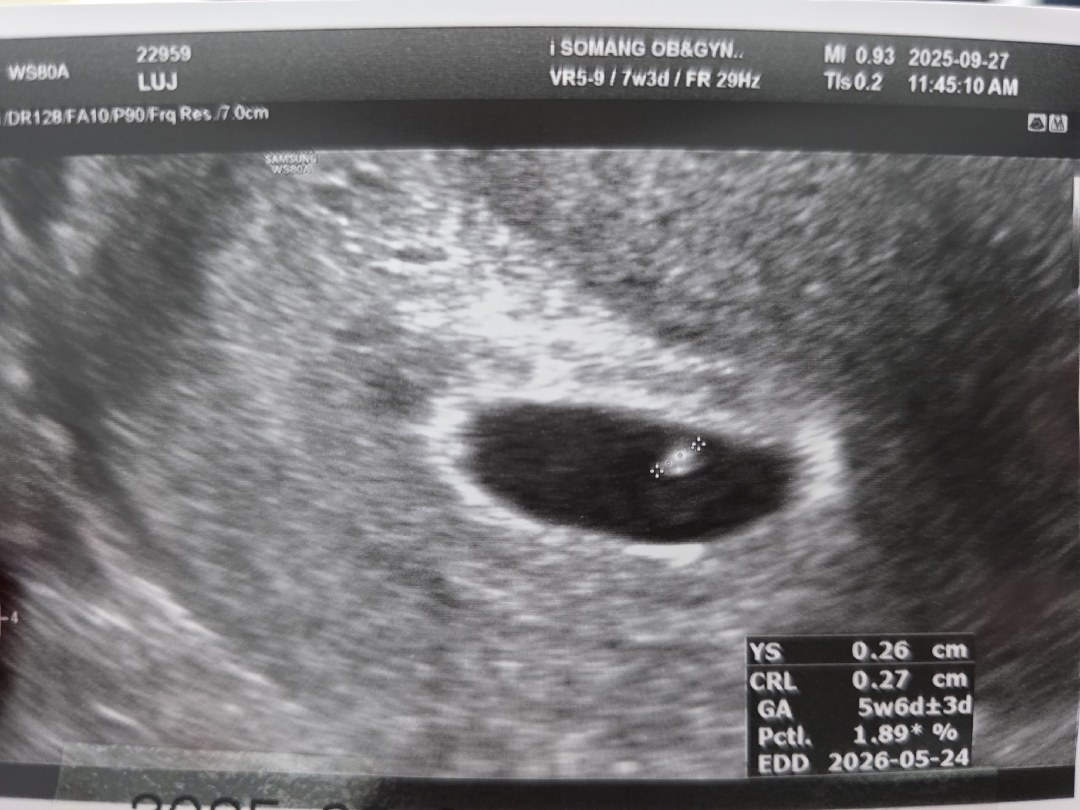

7주3일 심장소리 듣고왔어요!

콩알보다 작은게 심장이 뛰니까 너무 신기하고 감격스럽고ㅠㅠㅠㅠ 근데 막생기준으론 7주3일인데 애기크기 기준으론 5주6일이래요 그래서 처음 예정일이 내년 5월13일이었는데 오늘 초음파 보니까 5월24일로 나와있더라구요 병원에선 별말씀 없었으니 정상인걸까요? 주수에 비해 애기가 늦으면 유산될수도 있다고 들어서 걱정이네요ㅠ